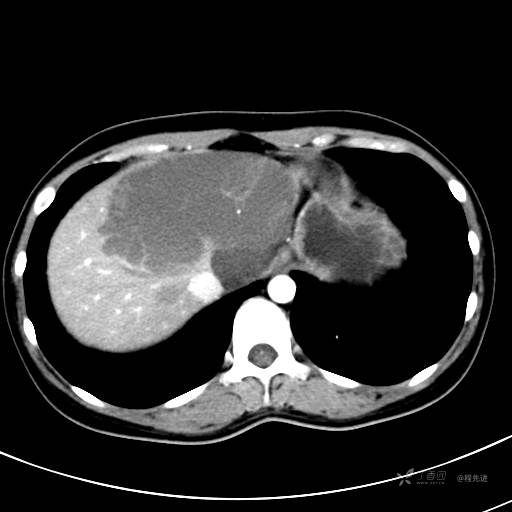

CT平扫+增强,每个序列3张图

CT值 平扫48HU 动脉期66HU 静脉期68HU 延迟期62HU